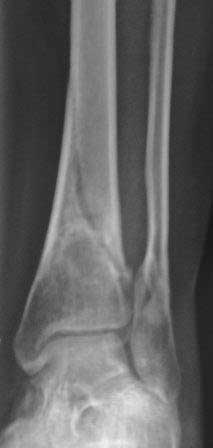

[Ortho] Вялоконсолидирующаяся перелом дистального метадиафиза костей левой голени

Пациентка 32 года, травму получила в результате ДТП, лечилась в гор.б-це №? Москвы с 19.07.по04.08.11г скелетным вытяжением, после наложена гипсовая повязка,(р-снимок 1,2.) после спадения отека гипс переведена в циркулярную, (видимо на другой вид лечения не хватило средств), гипс снят 19.11.11г(снимок-3)

.Жалобы на боли при ходьбе через несколько шагов, увеличение отека в голени и г/стопном суставе, боли ноющего и неприятного характера, хромота, при осмотре отечность голени в с-н/з и г/с суставе, при пальпации умеренная болезненность в н/з голени, подошвенное сгибание в г/с суставе ограничена и болезненна. Работа связана с ходьбой, просить помочь чтобы не потерять работу. Пока в голове только КДО аппаратом Илизарова, уважаемые коллеги  помогите советом! Доступно БИОС, пластины DCP. и прилагается последние р-снимки.